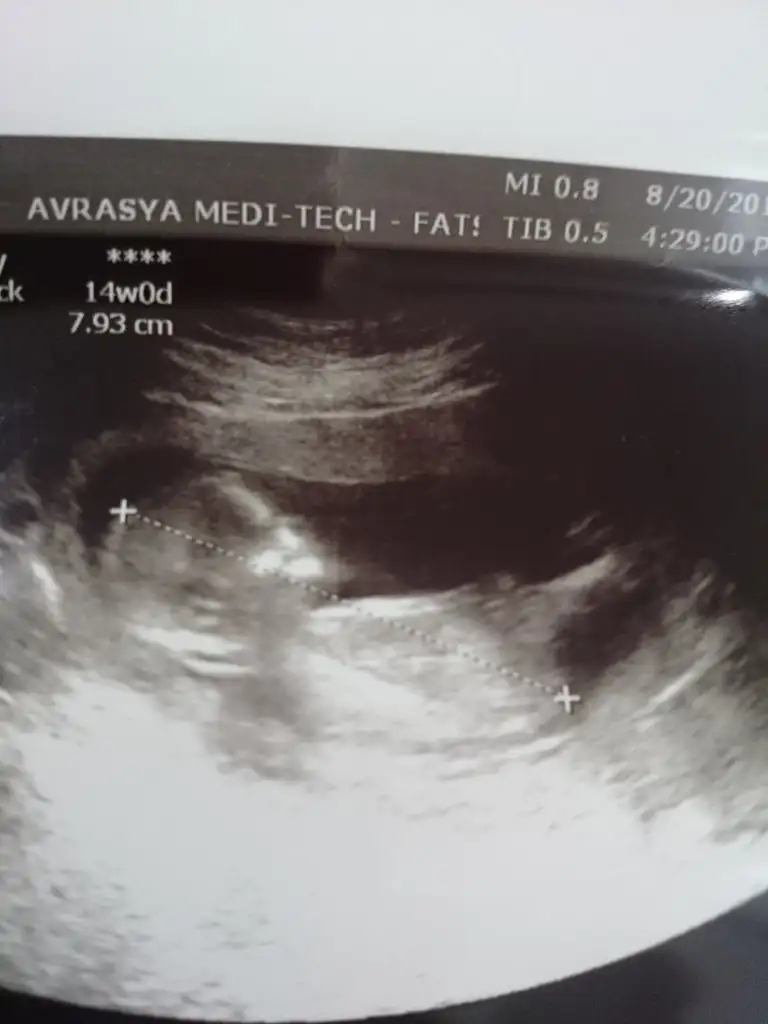

Merhaba bana da tahmin yapabilir misiniz 🤗

Eklentiler

• B8151435-6B59-4DAA-A49D-9EF56B437649.webp

B8151435-6B59-4DAA-A49D-9EF56B437649.webp

37,2 KB · Görüntüleme: 83